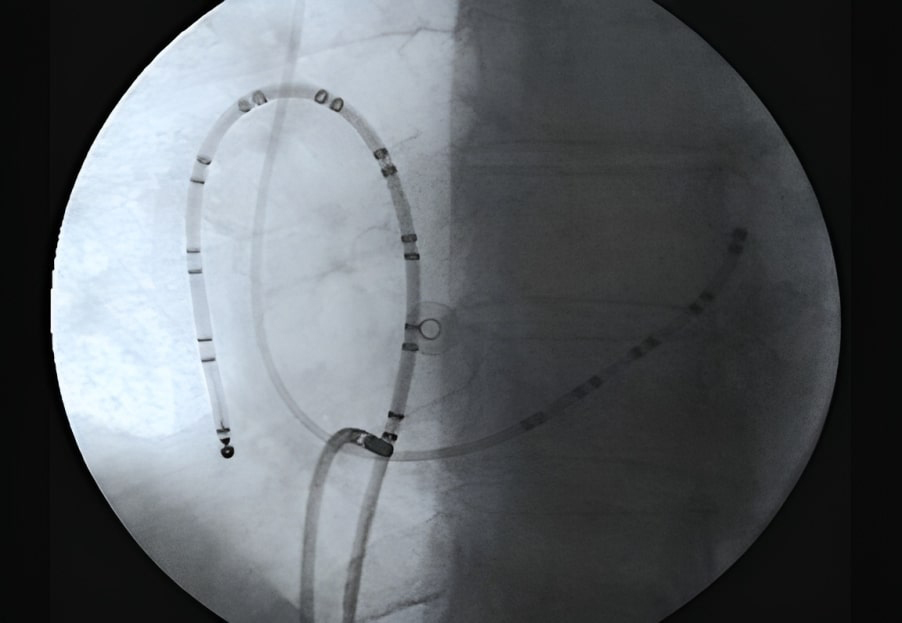

During an electrophysiological study of atrial flutter, multipolar catheters are commonly used. These catheters are inserted into the right atrium forming a loop around the tricuspid valve annulus. It is important to position the catheter used for mapping the right atrium in front of the crista terminalis. Another decapolar catheter is inserted into the coronary sinus, mapping left atrial activation, and placing the distal end of the catheter in the coronary sinus can be helpful in determining the activation sequence of the arrhythmia [94] (Fig. 5).

Fig. 5.Usual catheters positioning during a typical CTI ablation. Left anterior oblique X-ray projection is showed. Multipolar catheters around the tricuspid valve (ten dipoles) and in the coronary sinus (5 dipoles) at the left atrioventricular groove delimiting the mitral annulus inside it. Distal part of ablation catheter is on the CTI. CTI, cavotricuspid isthmus.